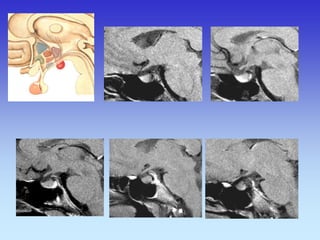

HIPOFIZA

Normalno

Tvorba selarnog područja